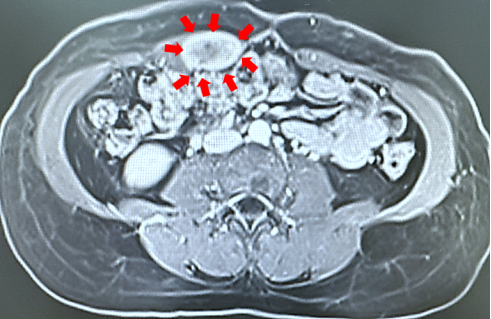

经过细致的问诊和体格检查后,戴伟钢副主任医师发现该肿物位于右侧腹直肌内,肿物平脐周围,大小约5*4cm、位置固定、无法推动、边界不清晰。为其完善了腹部核磁共振等相关检查后,戴伟钢副主任医生将其收治入院,并决定为其进行手术切除。

image.png

▲腹部核磁共振检查结果可见腹直肌内肿物